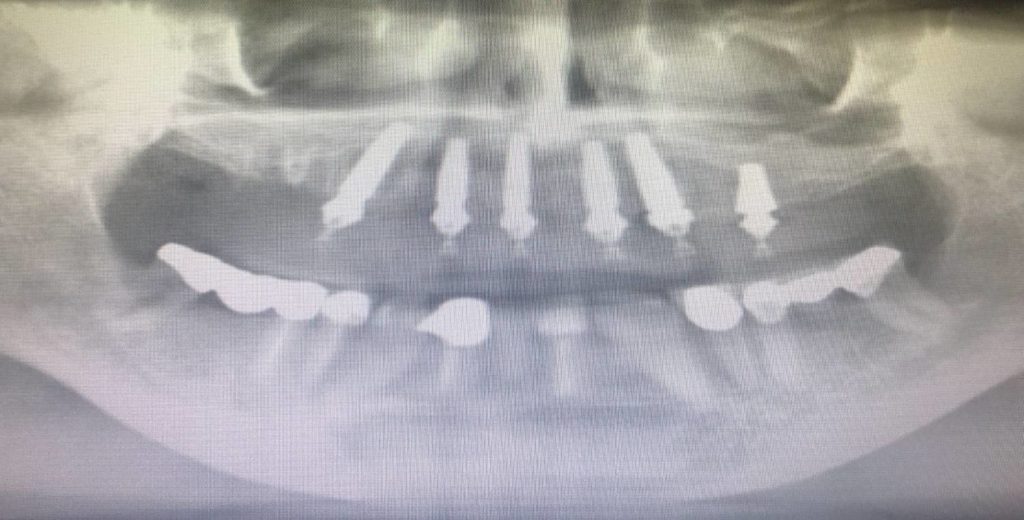

This is a ‘Teeth in a Day’ case. This is her final. Extraction of all top teeth. We placed 8 implants and fabricated her new smile. She did not want extremely white teeth.